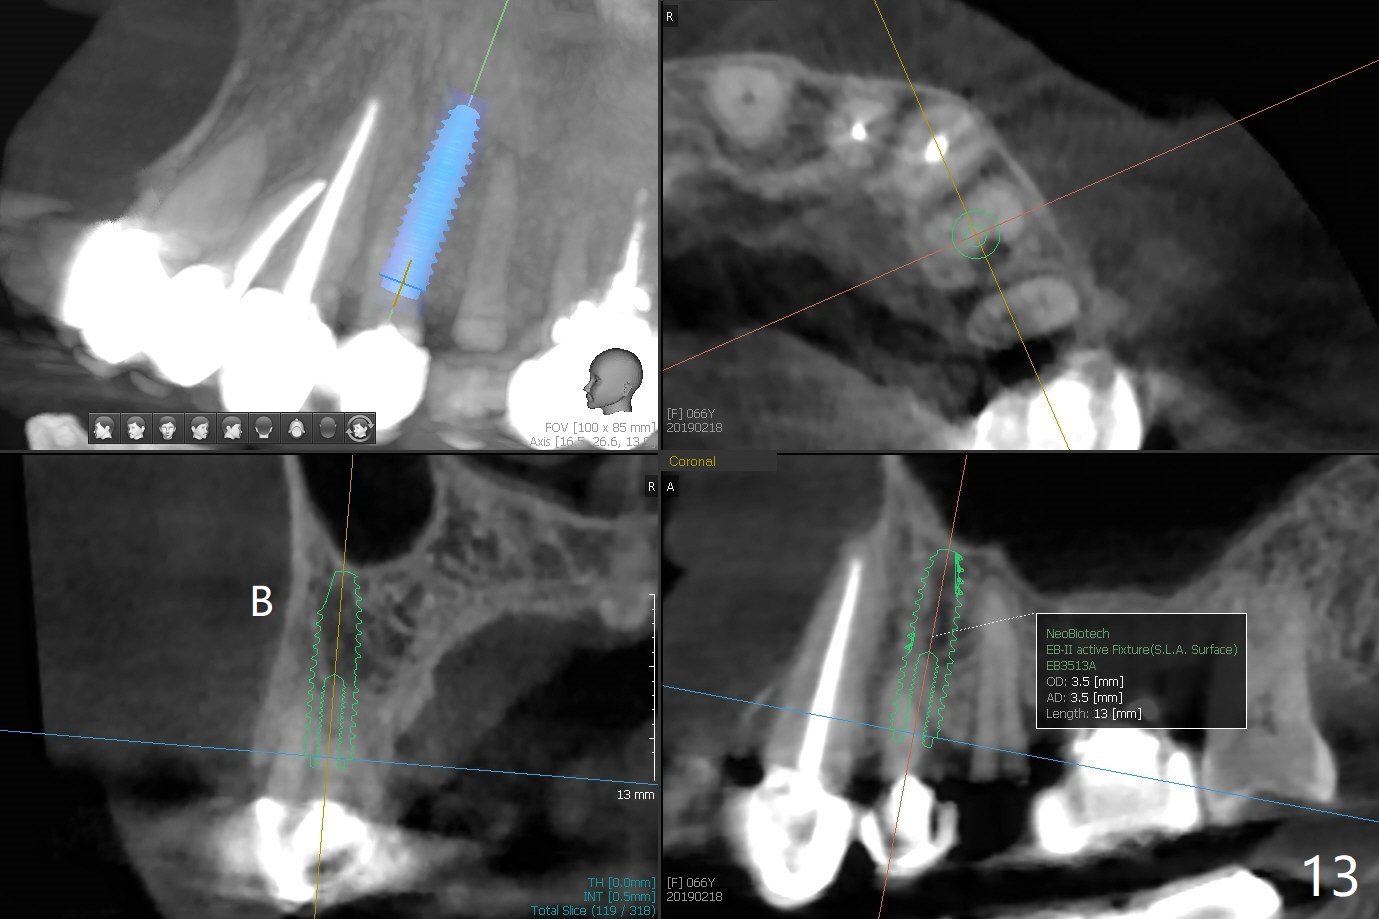

68岁女左上4颊侧瘘道(图一:*),与根尖颊侧骨板缺失相通,其实腭侧根尖周围病变更大(也与颊侧窝相通),术中没有注意腭侧根接近3(图二:P),稀里糊涂的基本顺着腭侧根(颊侧)走向钻洞(图四,与图三理想方向对比),突然记起术前设计钻洞必须在腭侧牙槽窝远中颊侧,在远中建立新洞眼(图五),之后无法再次建立新洞眼,只好利用同一个侧面切割钻头将钻洞往远中移位,同样效果不佳(图六),最后只好放弃,放置粘性骨粉(图七:*),覆盖PRF膜,6个月胶原膜,PGA缝线,牙周胶水。术后重新分析表明顺着腭侧牙槽窝种植与尖牙还是有分离(图八,九:*),因为牙槽窝是斜型的(图十:黑色),不过离颊侧骨板也接近(图八:B)。所以钻洞必须斜型针对远中骨壁,表浅些(图十一:红色箭头);一旦进入骨板,改变角度(图十二:红色箭头),适当矫枉过正,随着植体增大,钻洞会往近中偏移(白色箭头)。最好植体方向理想(图十三)。不过植骨后钻洞偏移可能性比较少。缝线和牙周胶水似乎是一个稳妥固定胶原膜方法。术后病人抱怨水肿严重,术后八天颊侧根尖隆起是由于骨粉推出骨板之外(图十五,十六:*),上颌窦底板无意穿孔(^)伴有上颌窦膜(M)增厚,与术前对比(图十七:上颌窦窦腔清晰)。术后一个月6个月吸收膜不见了,大多数缝线已经脱落,最后两根缝线撤除后,牙槽窝开口已经关闭,好像主要成分是骨粉(图十八)。术后5个月牙槽嵴宽,角化龈也宽,好像可以植入4x11.5毫米植体(图十九)。